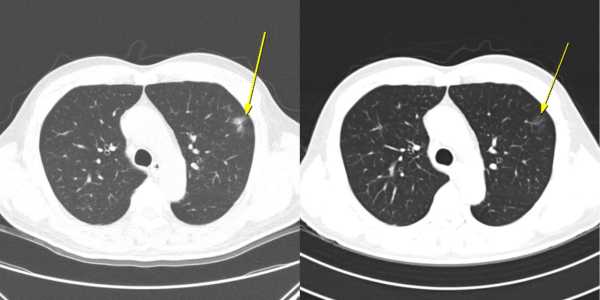

¡ã ¹«Áõ»ó ÀϽÃÀû ¸é¿ª°ü·Ã Æó·Å »ç·Ê: ÀÌ È¯ÀÚ´Â AteBeva Ä¡·á 3°³¿ù° ½ÃÇàÇÑ Àú¼±·® ÈäºÎ CT(¿ÞÂÊ)¿¡¼­ Æó ÁÖº¯ºÎ¿¡ ¹Ì¼¼ ¿°Áõ¼º À½¿µÀÌ ³ªÅ¸³µÀ¸³ª, 6°³¿ù° CT(¿À¸¥ÂÊ)¿¡¼­´Â ÀÚ¿¬ÀûÀ¸·Î ¼Ò½ÇµÇ´Â ¾ç»óÀ» º¸¿´´Ù. Ä¡·á´Â Áö¼ÓµÆÀ¸¸ç, ÀÌÈÄ ºÎºÐ °üÇØ(PR)¸¦ ´Þ¼ºÇß°í ÃÑ 19.7°³¿ù°£ ¹«ÁøÇà »ýÁ¸(PFS)À» À¯ÁöÇß´Ù.

¿¬±¸ÆÀÀº Ä¡·á Áß ³ªÅ¸³­ ÀÌ»ó¹ÝÀÀ ¾ç»ó¿¡ µû¶ó ȯÀÚ¸¦ ¡ãÀÌ»ó¹ÝÀÀÀÌ ÀüÇô ¾ø´Â ¡®¹«ÀÌ»ó¹ÝÀÀ±º¡¯ ¡ãÀÓ»ó Áõ»óÀ̳ª Ç÷¾×°Ë»ç ÀÌ»óÀ» µ¿¹ÝÇÑ ¡®Áõ»ó¼º ÀÌ»ó¹ÝÀÀ±º(Áõ»ó±º)¡¯ ¡ãÁõ»óÀº ¾øÁö¸¸ CT¿¡¼­ Æó ÁÖº¯ºÎ ¹Ì¼¼ ¿°Áõ¼º À½¿µ, ÀϽÃÀû ´ëÀ庮 ºñÈÄ, Àå°£¸· ¿°Áõ, ¹ÝÀÀ¼º ¸²ÇÁÀý Á¾´ë µî ¸é¿ª¹ÝÀÀÀ¸·Î ÇØ¼®µÇ´Â º¯È­¸¸ ³ªÅ¸³­ ¡®¹«Áõ»ó ¿µ»ó ÀÌ»ó¹ÝÀÀ±º(¹«Áõ»ó ¿µ»ó±º)¡¯À¸·Î ºÐ·ùÇß´Ù. Àüü 198¸í Áß ¹«Áõ»ó ¿µ»ó±ºÀº 12¸í, Áõ»ó±ºÀº 56¸í, ¹«ÀÌ»ó¹ÝÀÀ±ºÀº 130¸íÀ̾ú´Ù.